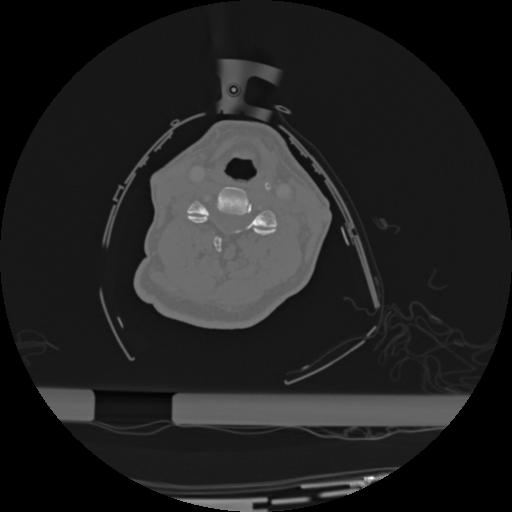

22 ANGIO,CE,Vol,0.5,ANGIO,,